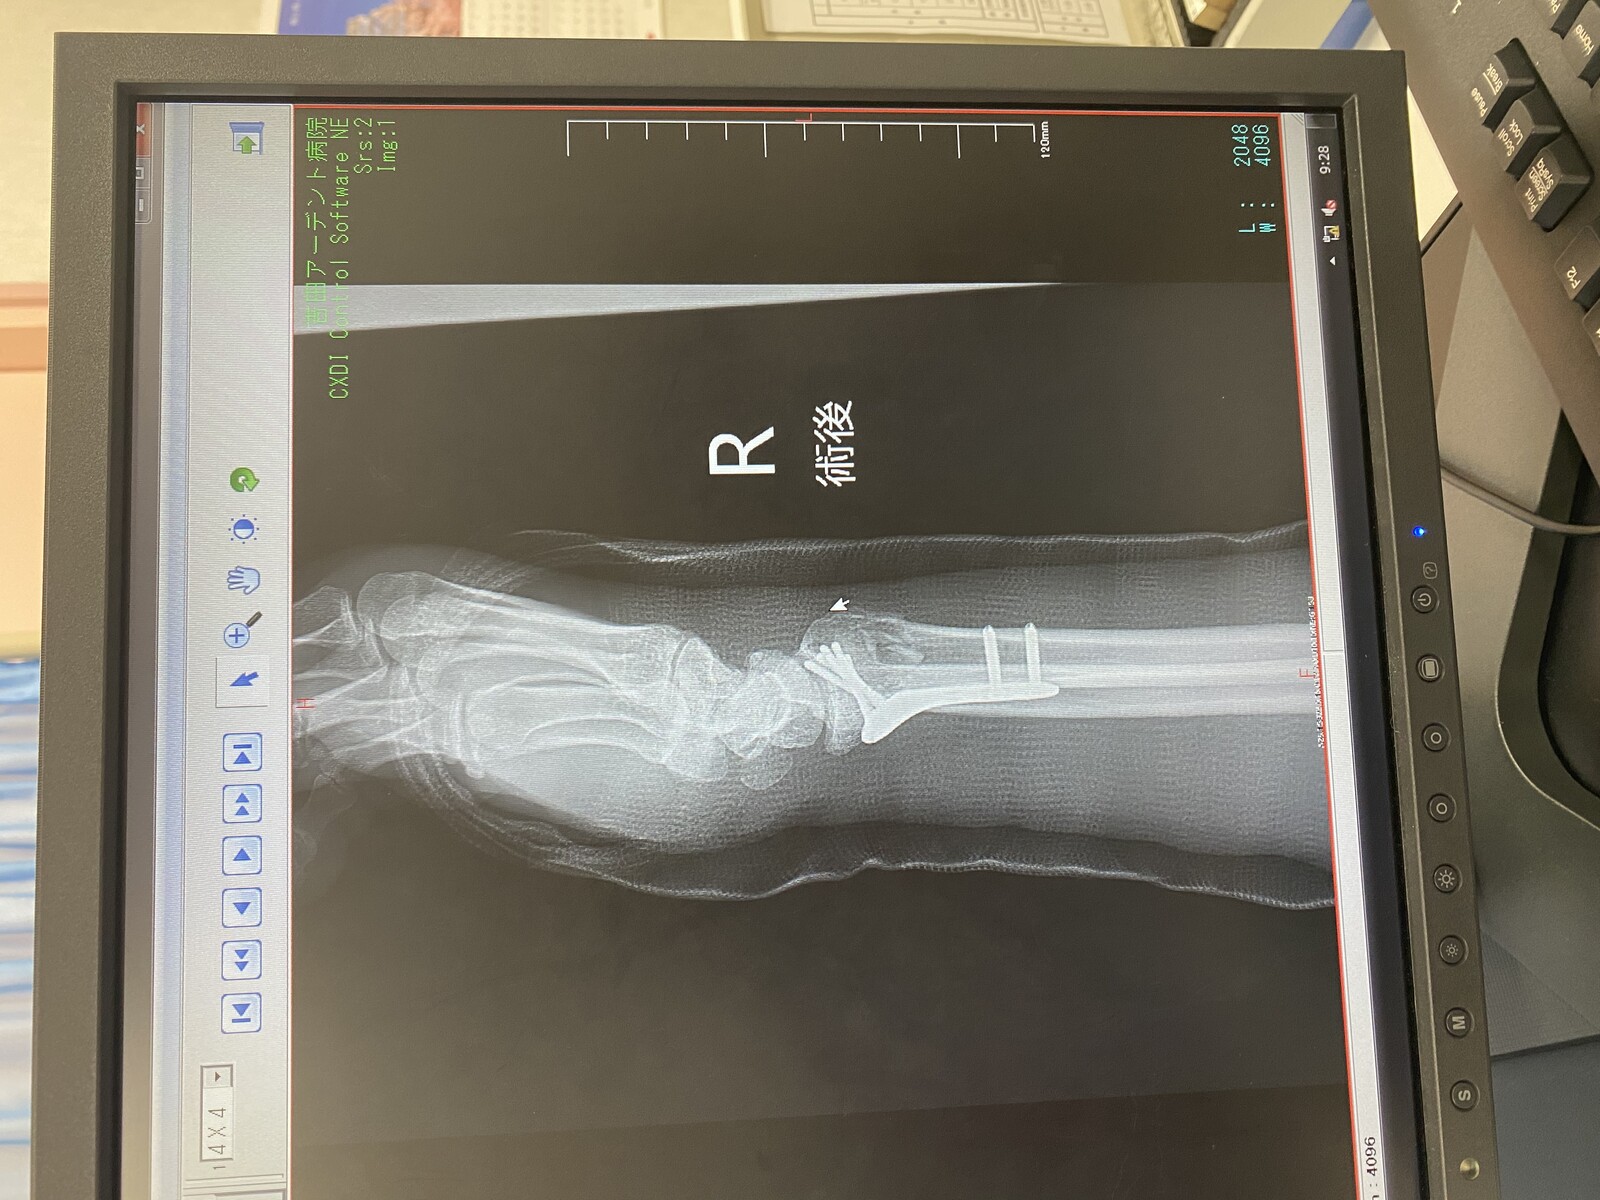

最後におかんの採血なんやけど、右腕はギブスであかんし